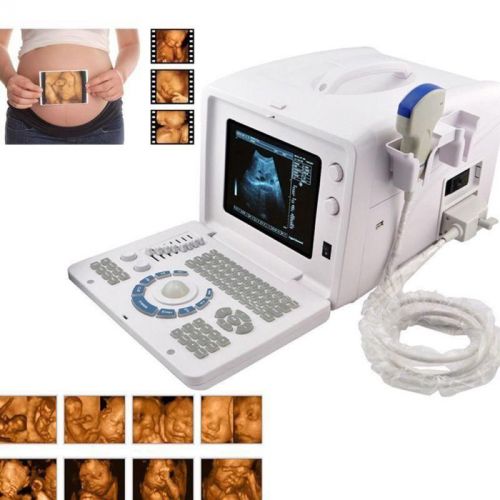

Brand | Ultrasound 9000E2 |

| MPN | Full Digital Ultrasound | ||

| Model | HIGH RESOLUTION | ||

2 probes+3D Digital Ultrasound Scanner+3.5MHz Convex 7.5MHz Linear probe CE DFA